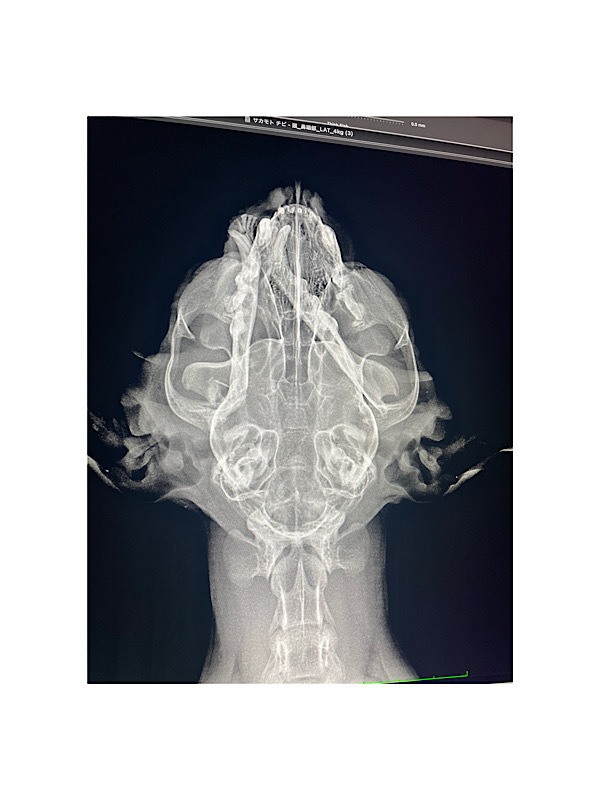

↑手術前のレントゲンです

舌顎が折れています。